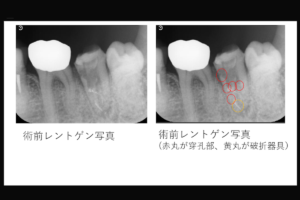

精密な根管治療において、偶発的な穿孔(パーフォレーション)の封鎖と破折器具の除去は難易度の高い処置です。マイクロスコープを駆使し、穿孔部には生体親和性の高いMTAセメント等を用いて封鎖を行い、破折片は超音波チップ等で慎重に除去します。歯の保存を最大限に試みる、専門性の高いリカバリー技術です。